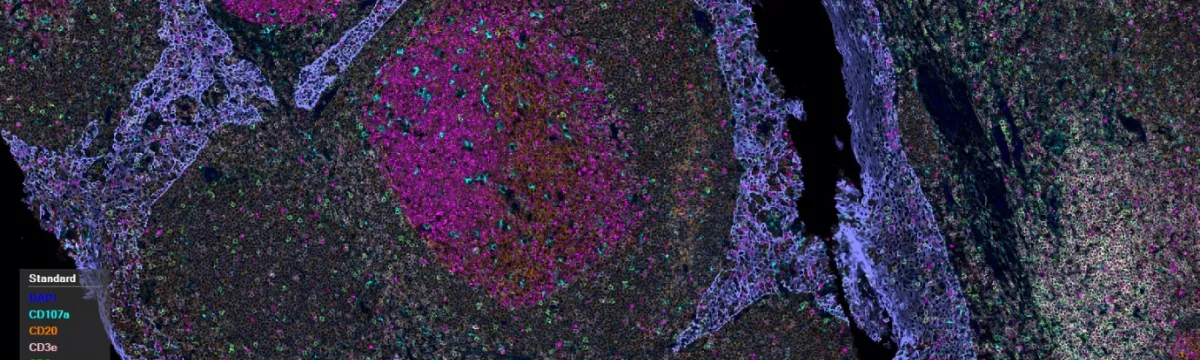

Single or multiplex staining

DAB staining

Fluorescent staining

6-plex Opal staining (plus DAPI)